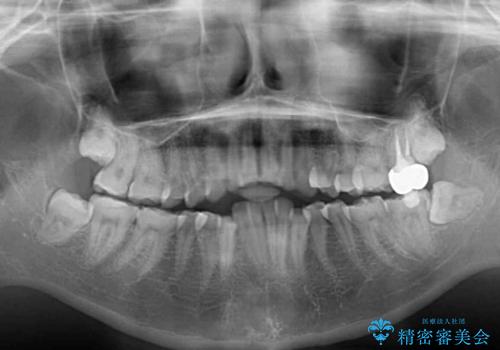

- 一時期の拒食症に伴い歯が酸で溶けてボロボロになってしまったとのことで来院された患者様です。

酸によりエナメル質の大半が溶けており、下顎前歯以外は酷いむし歯のような状態でした。

当初はほとんどの歯をむし歯治療のようにオールセラミッククラウンにて補綴治療を行う予定でしたが、仮歯に置き換えた時点で、口元の突出感や下顎前歯の叢生が気になるとのことで、上下左右の第一小臼歯4本を抜歯したワイヤー装置での抜歯矯正を行うこととしました。

矯正治療終了後に、残った歯をオールセラミッククラウンにて補綴治療を行うこととしました。

途中来院が困難な時期があったり、歯周外科処置を行って治癒を待ったりと、治療期間は長くなりましたが、初診時とは比べものにならないくらいきれいに仕上げることができました。